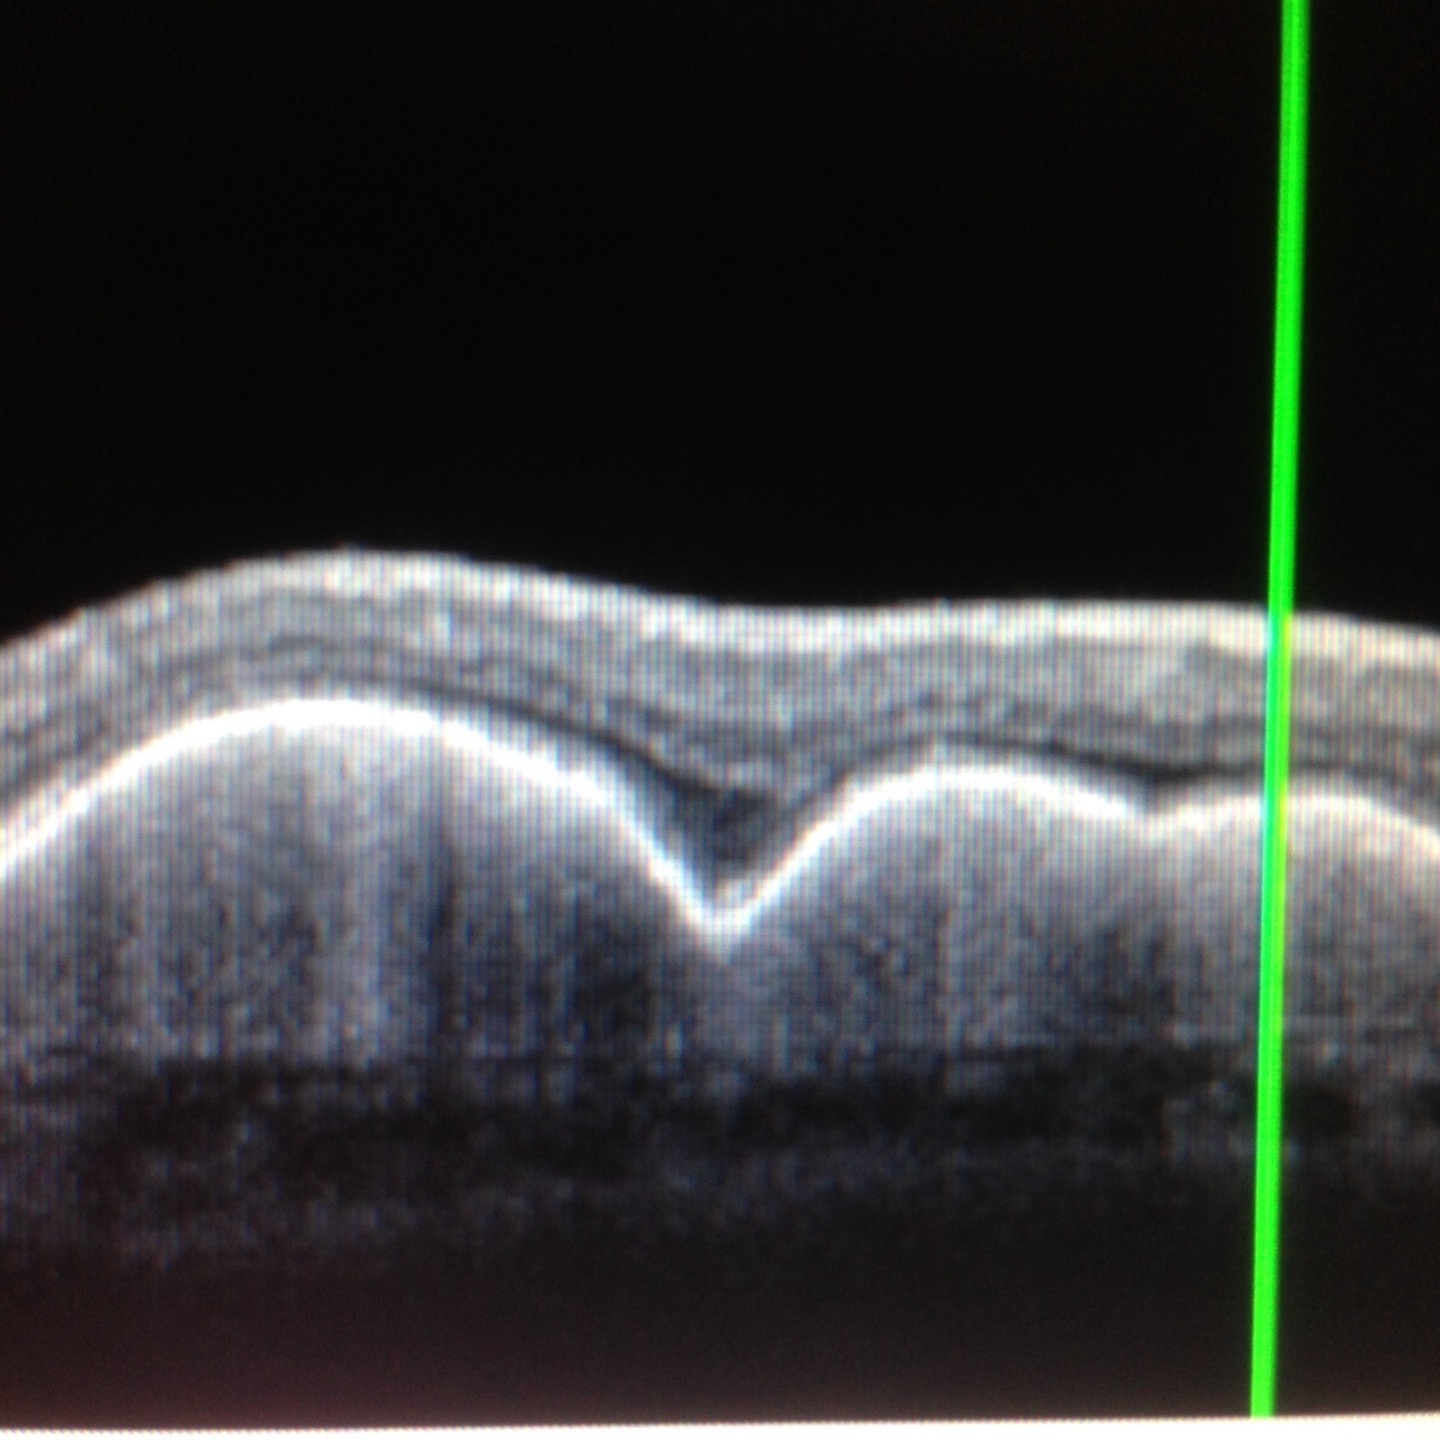

- échographie oculaire

Tomographie par Cohérence Optique - OCT :

pathologie rétinienne et glaucome